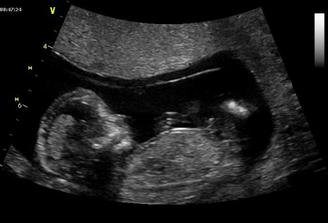

Tak se na nás snad už štěstí konečně usmálo a na IVF už nepůjdeme....... Měli jsme těsně před stimulkou na 2.IVF a čekali na mrchu. Místo toho jsme 15.3.2009 objevili naše krásné //. 17.03.2009 bylo na UTZ vidět plodové vejce, cca 2,7mm, další kontrola 31.3.2009. Tam už byl vidět náš bobeček, 6,3mm veliký a srdíčko mu bilo jako o závod. Dostali jsme krásné fotečky a jsme moc šťastní. Tak konečně je 23.4.2009 a jsme i s taťkou na dalším UTZ, jsme 9+6. Paní doktorka z nás měla velkou radost, říkala, že tak mrskající se miminko už dlouho neviděla. Velikostí odpovídáme úplně na den, máme už těhu průkajdu a dneska jsem se objednala na časný genet. skr. k MUDr. Břešťákovi. Termín porodu je 20.11.2009 a manža má narozky 24.11. 2009. No a já je mám zítra, takže super dnešní dárek. Tak dneska 11.5. 2009 jsem byla u zubaře pro razítko do těhu průkajdy a už ho mám. Další den 12.5.2009 jsme byli u mé praktické paní doktorky, natočila mi EKG a dala nám razítko do těhu průkajdy. Dneska 14.5.2009 jsme byli s manžílkem na genetickém screeningu. Pan doktor a sestřička byli moc hodní. Sestřička mi nabrala krev, vůbec jsem nezaznamenala, že je po odběru, je moc šikovná. Výsledky budou do 14-ti dnů. Pan doktor nám ukázal miminko v celé své kráse, jsme obříci, máme skoro 8 cm, NT 1,8 mm. Dle pana doktora jsme o 6 dnů větší a odpovídáme 13+5 (dle MS 12+6), tak nám upravil termín porodu na 14.11.2009. Slyšeli jsme tlukot srdíčka a bylo to nádherné, 160 úderů /min.. Pan doktor nám dal fotečky na CD, tak jsme moc šťastní. Jelikož nám pan doktor posunul termín porodu o týden dříve, tak jsme se byli 19.05.2009 zaregistrovat k porodu do FN Motol. Dneska 21.05.2009 jsme byli na kontrole a dostali jsme fotečky obličejíčka našeho mimíska. Je to celý tatínek. Mimísek na nás koukal a pěkně skotačil, paní doktorka nám ukázala jak má právě nožičku u hlavičky. Na den dětí 01.06.2009 jsme se dozvěděli, že výsledky screeningu jsou v pořádku. Jsme moc rádi. Dne 04.06.2009 jsem si volala na výsledky krevních triple testů a sestřička mi sdělila, že jsou v pořádku. Jsme s taťkou moc šťastní. Tak dneska 11.06.2009 jsme byli na kontrole u naší paní doktorky a s taťkou jsme byli zvědaví, jestli se nám už ukáže holčička nebo chlapeček. Paní doktorka se moc snažila, říkala, že by to viděla na holčičku, ale že opravdu spíše tipuje, protože miminko nechtělo roztáhnout nožičky. Tak uvidíme, jestli nám to řekne pan doktor na velkém UTZ, kam se objednáme. Bylo vidět, jak si miminko podpírá ručičkou bradičku a paní doktroka nám udělala nějaké fotečky. Jsme s tatínkem moc rádi, že se má miminko fajn. Dneska končíme 4. měsíc. Po měsíci -7.7.2009 jsme konečně zase viděli naše miminko. Paní doktorka nám ukázala močový měchýř, srdíčko, žaludek. Miminko se mrskalo, dokonce nám zamávalo. Paní doktorka nám řekla, že na 90% čekáme holčičku!